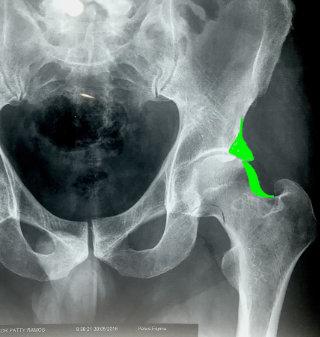

ienes dolor o molestia en la ingle, muslo o glúteo al caminar, sentarte, durante o después de realizar actividad física, o incluso al subir al auto? Podría tratarse de un pinzamiento de cadera, un problema que, si no se atiende a tiempo, puede dañar tu articulación permanentemente y requerir una cirugía de alto riesgo.

Muchos creen que es "cosa de la edad", pero la verdad es que la cadera no duele por envejecer, duele por enfermedad.

Existe una solución avanzada y poco invasiva para esta enfermedad: la artroscopia de cadera. Es un procedimiento que realizo con técnicas de vanguardia, que corrige el problema, alivia el dolor, tiene una recuperación mucho más rápida que la cirugía tradicional y te permite recuperar tu vida sin largas hospitalizaciones. Soy especialista en cirugía de cadera, hombro, rodilla y lesiones deportivas y justamente una de las razones por las que tomé dicha especialidad, fue por una pasión auténtica por profundizar en mi campo y alcanzar el más alto nivel de preparación.

Soy el único especialista certificado en artroscopia de cadera en todo el estado de Colima, con entrenamiento en las mejores técnicas internacionales y tecnología de vanguardia.